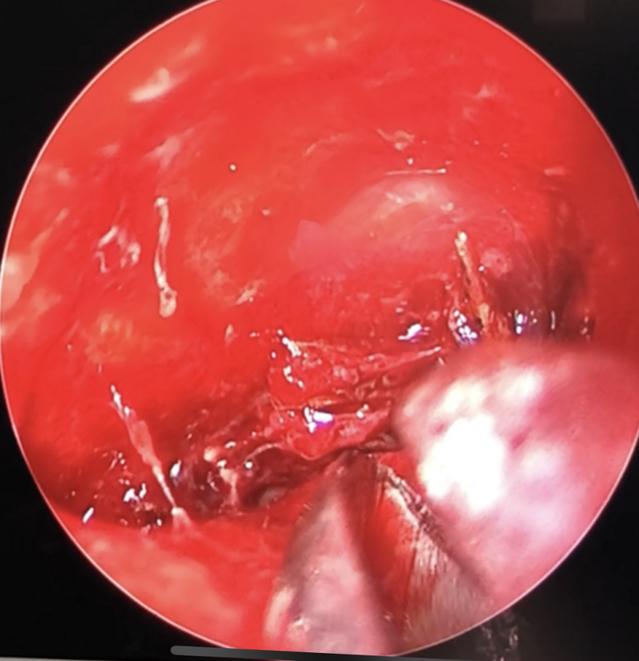

Hốc mắt của bệnh nhân chứa đầy mủ và dị vật qua hình ảnh nội soi

BS-CKII Hoàng Bá Dũng, Trưởng khoa Tai Mũi Họng, Bệnh viện Chợ Rẫy cho hay: Chẩn đoán hình ảnh ghi nhận người bệnh bị mủ chiếm toàn bộ hốc mắt trái sau nhãn cầu. Kết quả chụp cộng hưởng từ phát hiện hốc mắt của người bệnh có nhiều dị vật. Sau hội chẩn, chúng tôi quyết định tiến hành nội soi theo vết thương, lấy dị vật cho bệnh nhân.

Sau hơn 1 giờ nội soi, các bác sĩ lần lượt gắp ra 10 mảnh dị vật (là những mảnh cây có kích thước từ 0,5cm đến 2cm) nằm trong hốc mắt ở vị trí rất khó - phía sau nhãn cầu. Hơn 2 tuần sau phẫu thuật, bệnh nhân đã bình phục sức khỏe, mắt không còn mủ, hết sưng, thị lực được bảo toàn.

Theo BS Bá Dũng, đây là ca bệnh ít gặp, rất khó bởi dị vật không cản quang và nằm ở vị trí “hiểm” việc can thiệp lấy dị vật rất dễ xâm lấn, gây tổn thương đến thị lực người bệnh. Nếu không lấy được dị vật, bệnh nhân sẽ bị nhiễm trùng, hoại tử hốc mắt, tổn thương thần kinh thị dẫn tới mù lòa.